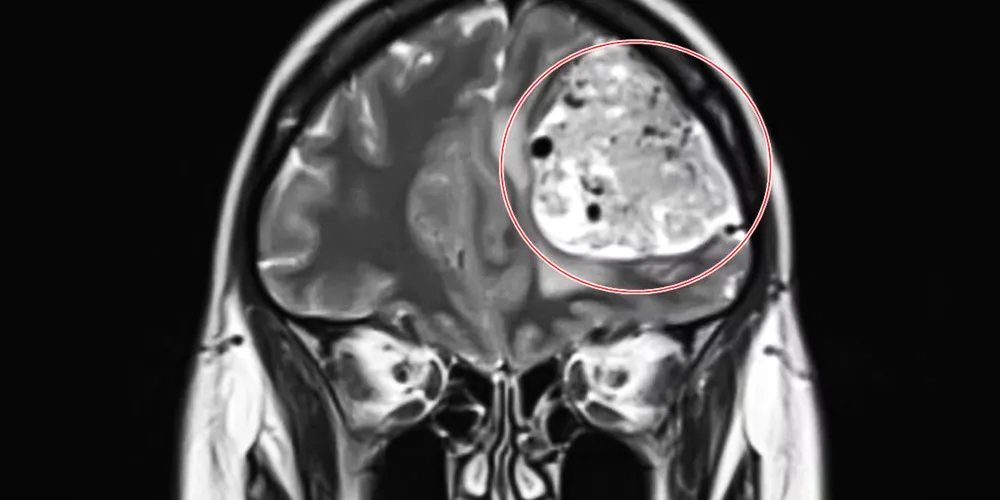

Após optar por desembolsar cerca de R$ 2,5 mil por uma ressonância magnética particular, a vida da mulher sofreu uma transformação: em poucas horas, ela recebeu uma chamada solicitando que se dirigisse imediatamente ao hospital, uma vez que os exames apontaram uma grande massa em seu lobo frontal esquerdo.

Nikita recorda-se do impacto ao visualizar a imagem do tumor e ouvir do médico que se tratava de uma grave lesão cerebral.